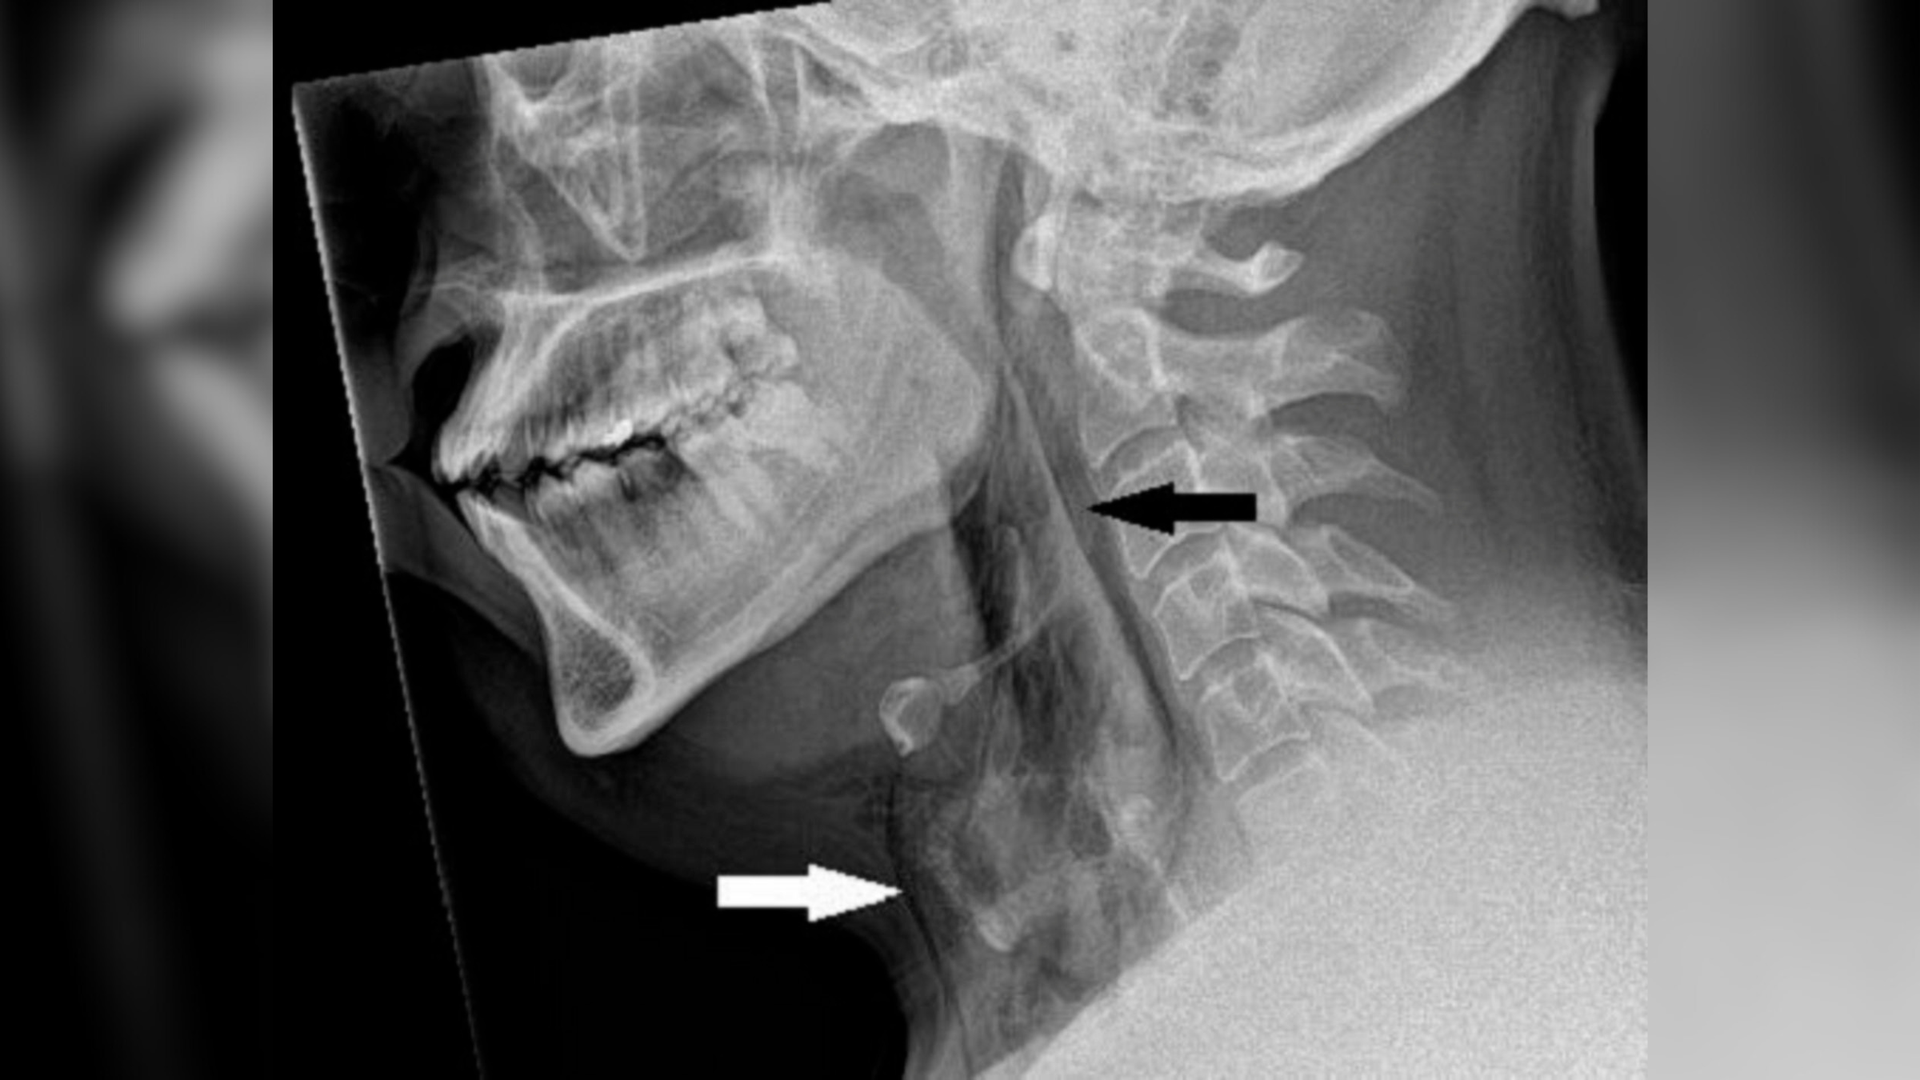

Diagnostic dilemma: A man held in a sneeze — and it punctured his windpipe

This Man Held in a Sneeze—And Blew a Hole in His Windpipe

Man Stifles Sneeze and Tears Windpipe in Rare Medical Case

Man Holds Sneeze, Tears Windpipe in First Case of Its Kind: Study